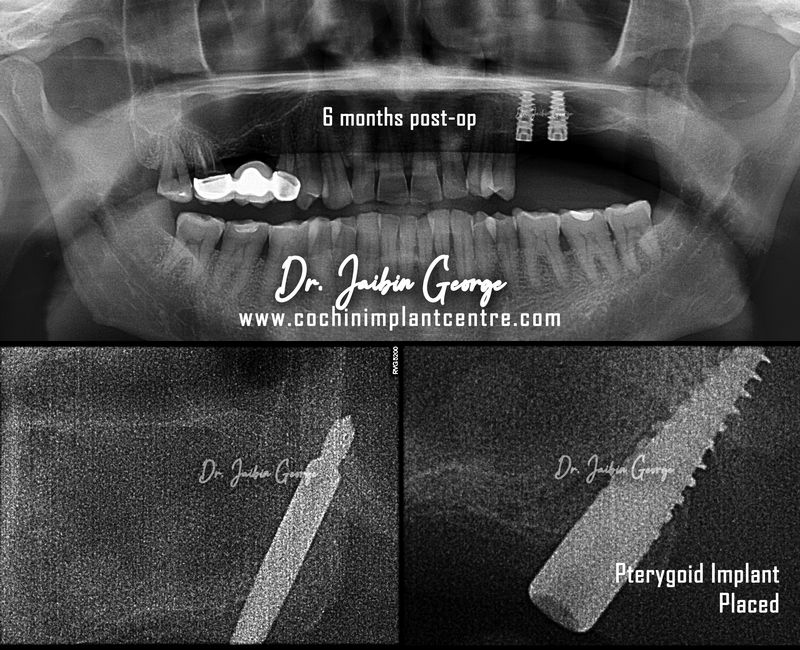

Case No: 19